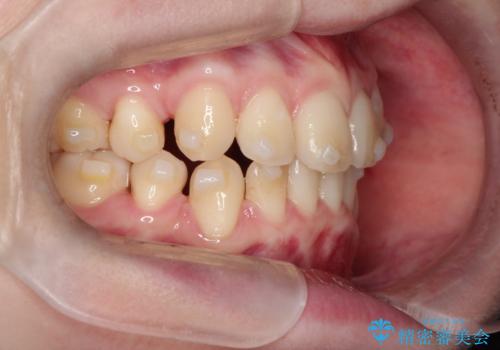

- 八重歯が気になるとのことでご相談いただきました。診察すると、歯列のスペース不足により犬歯が外側に飛び出している状態でした。このままでは歯を並べるスペースが足りないため、抜歯矯正が必要と判断。治療は目立ちにくいインビザラインで行い、歯の移動をサポートするためにゴムかけ(顎間ゴム)を併用する計画を立てました。

抜歯後、インビザラインを用いて少しずつ歯を移動させ、空いたスペースに八重歯を整列させました。さらに、ゴムかけを行うことで上下の噛み合わせを適切に調整。治療後は、八重歯が綺麗に並び、バランスの取れた歯並びと自然な噛み合わせを実現できました。患者様にも「仕上がりがとても綺麗で、口元の印象が変わった」とご満足いただきました。